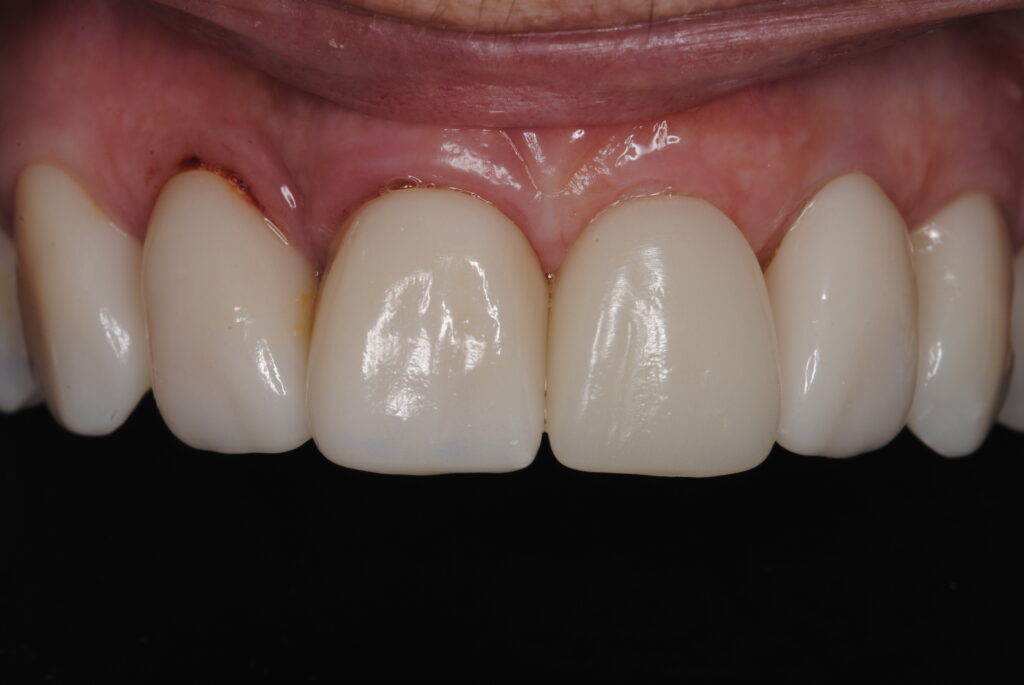

Hoy compartimos un impresionante caso clínico de cirugía guiada, ilustrado con fotos que documentan cada etapa del proceso. En el mismo día, removimos el diente dañado, realizamos injertos de tejido blando y hueso, colocamos el implante y un diente provisional. Como puedes ver en la última foto, el diente provisional se mimetiza perfectamente con los dientes naturales del paciente.

La cirugía guiada nos permite ofrecer a nuestros pacientes resultados superiores en términos de estética y funcionalidad, asegurando una integración perfecta y una recuperación rápida. Si deseas conocer más sobre el procedimiento de dientes en un día o tienes alguna pregunta, no dudes en contactarnos. ¡Estamos aquí para ayudarte a lograr la sonrisa que siempre has deseado!